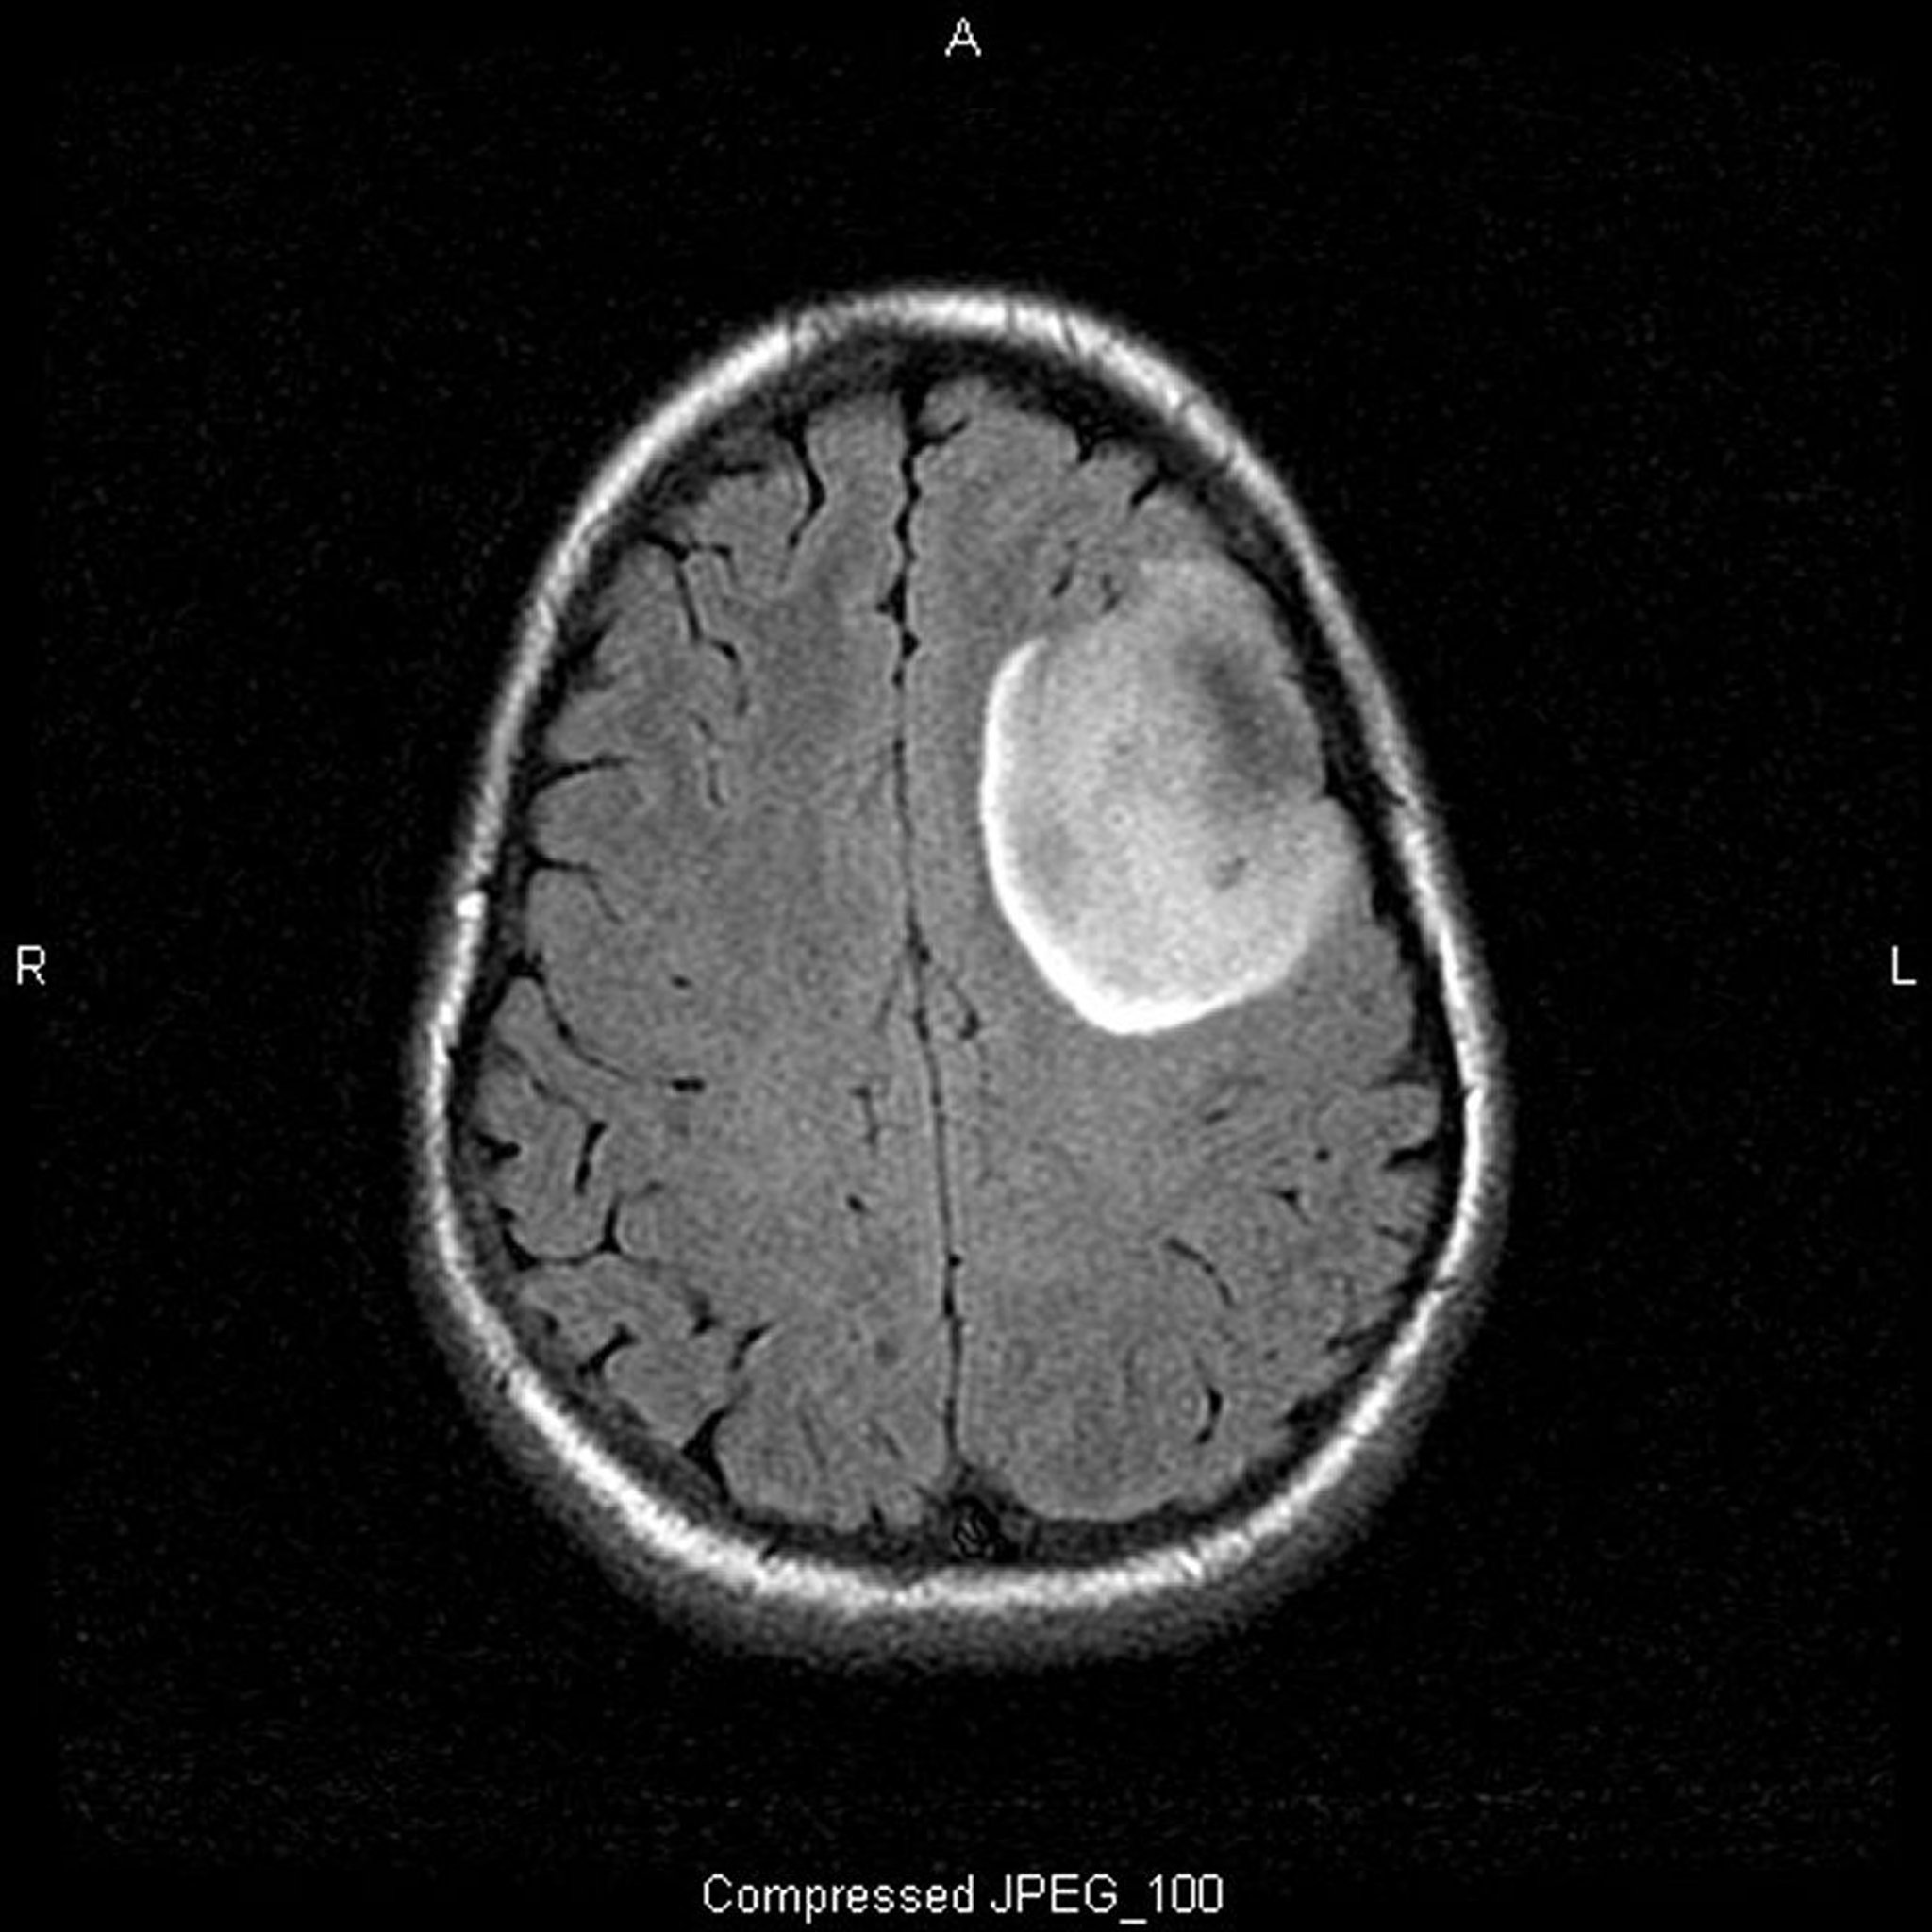

乏突起膠腫,低悪性度

MRIで撮像されたこのT2-FLAIR(fluid-attenuated inversion recovery)画像には,腫瘤または浮腫を示唆する白い高信号域が認められる。左前頭葉の信号は境界が非常に明瞭であり,腫瘤を示唆する。造影剤を使用しても増強されない。低悪性度(グレードII)乏突起膠腫である。

Image courtesy of William R.Shapiro, MD.